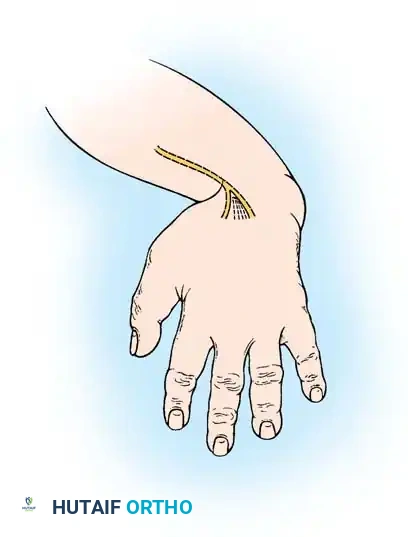

A newborn presenting with a transverse deficiency typically exhibits a slightly bulbous, well-padded stump. In more distal deficiencies, rudimentary, vestigial digital "nubbins" are frequently observed.

Fig. 76-2 Failure of formation (digital nubbins). The presence of functional wrist motion allows the limb to be used effectively as an assisting hand.

Hypoplasia of the more proximal musculature is a key clinical finding that helps differentiate true transverse deficiencies from amputations caused by congenital constriction band syndrome (amniotic band sequence). In the most common presentation—the upper forearm amputation—the forearm is usually no more than 7 cm long at birth and will reach a maximum length of approximately 10 cm by skeletal maturity.

In midcarpal amputations (the second most frequent level), the rudimentary digital remnants are almost always nonfunctional. However, because the radiocarpal joint is preserved, pronation and supination are usually possible, providing a highly functional assisting limb. Cognitive development and intelligence in these children are generally normal.